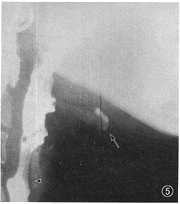

四、括约肌开闭

1.食管上括约肌(upper esophageal sphincter,UES):又称咽食管段或环咽部,由下咽缩肌及其远侧的食管环行肌组成,长2.5~4.0 cm。非吞咽时,UES处于闭合状态并保持约100 mm Hg(1 mm Hg=0.133 kPa)的高压。吞咽时,UES快速开放,持续0.2~0.3 s后关闭。开放的程度和时间因食(钡)团的大小、质地、到达的速度而不同。UES在EDR中常可清楚显示(图5)。除能直接观察其开放程度外,还可根据其近侧钡液滞留的数量和时间以及钡液进入气道(称aspiration,吸入)等情况,判断其开放的不适时和不适度性(图6),详见有关专著[9,13,14]。

图5 示UES开放(▲),钡剂正常通过时的表现。↑示舌骨位置

图6 UES(▲)功能紊乱,开放延迟,吞咽1次的钡剂不能1次完全通过,较多量钡剂在咽腔滞留,并有钡剂吸入气道(↑)

1.UES开闭功能不协调:在443例吞咽障碍病人中的出现率达19.5 %,主要与颅脑、颈部、食管等的病变及外伤有关[14](图6)。